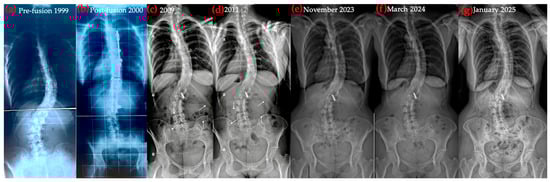

Figure 6. Lumbar and thoracic Cobb angles changes on radiographs taken between 1988 and 2025 (13–49 years).

Figure 7. Sagittal X-ray progression over time: (a) pre-surgery, 1999; (b) post-surgery, 2000; (c,d) sagittal postural deterioration, 2009 and 2011; (e) sagittal postural improvement, after 1 year Schroth + brace; (f) sagittal postural improvement, after 17 months Schroth + brace; (g) sagittal postural improvement, after 28 months Schroth + brace.

Figure 8. Coronal X-ray progression over time: (a) pre-surgery; (b) post-surgery; (c,d) coronal postural deterioration; (e) coronal postural improvement, after 1 year Schroth + brace; (f) coronal postural improvement, after 17 months Schroth + brace; (g) coronal postural improvement, after 28 months Schroth + brace.

Although sagittal realignment was the primary therapeutic target, coronal parameters also changed over time. The thoracic curve decreased from 48° (2016) to 32° Cobb (2025), representing a 16° reduction, while the lumbar curve remained stable at approximately 34° Cobb. Coronal imbalance resolved, with the C7 plumb line shifting from 3.5 cm left of the midline to 0 cm.

These changes are summarized in Figure 6, which illustrates the thoracic and lumbar Cobb angles across radiographs obtained between 1988 and 2025 (ages 13–49). Trunk asymmetry, assessed with a scoliometer, remained stable at approximately 15° ATR. Due to prior costoplasty, ATR values were considered approximate and used primarily for trend monitoring.

Longitudinal coronal and sagittal outcomes were documented using standardized radiographs and clinical photographs at five intervals: pre-operative, post-fusion with costoplasty, progressive deformity phase, pre-intervention, and post-treatment review. As shown in Figure 4, Figure 5, Figure 6, Figure 7, Figure 8 and Figure 9, outcomes ranged from early post-fusion postural improvement to deterioration after hardware removal, followed by measurable realignment achieved through Schroth-based physiotherapy and bracing between 2000 and 2025.